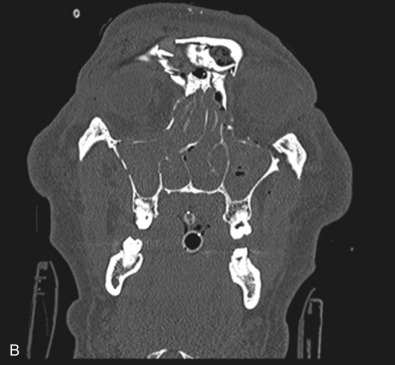

Le Fort II fractures are pyramidal in shape, involving the central portion of the midface while the lateral orbits and zygoma remain intact. The line of fracture extends bilaterally through the nasofrontal junction, medial orbital wall, inferior orbital rim, along the maxilla, through the dental alveolus anteriorly and posteriorly at the level of the maxillary tuberosity into the pterygoid plates ( Figs. 1.13.14 and 1.13.15 ). Only Le Fort II fractures violate the inferior orbital rim, causing the highest incidence of infraorbital nerve hypesthesia due to the proximity to the infraorbital foramen. Bones of the maxilla below the Le Fort II line of fracture can be intact, however they are often comminuted with other fracture patterns occurring in the Le Fort II segment. The force is typically delivered centrally at the level of the nasal bones, resulting in the separation of the central maxilla from the surrounding facial skeleton. Brain injuries are more frequent in central Le Fort II injury patterns.